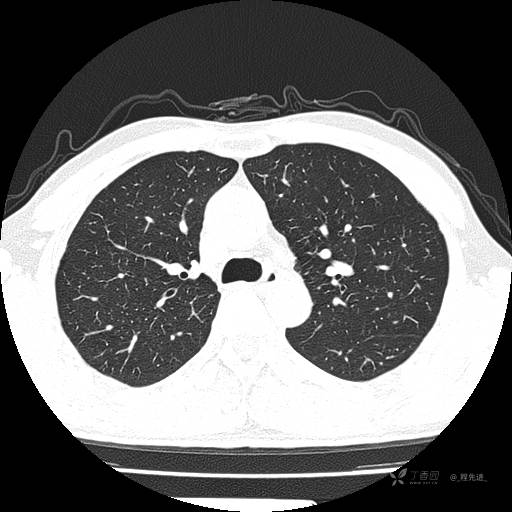

2月特别精彩病例|咳嗽、咳痰20余天,典型病例分享【结果已公布】

患者年龄:51岁

主诉:咳嗽、咳痰20余天

简要病史:20余天前开始出现咳嗽、咳痰症状,阵发性刺激性咳,白色粘痰,不易咳出,无发热,无咯血,无恶心、呕吐等不适,未诊治,咳嗽、咳痰症状持续存在。

体格检查:T:36.3 ℃ P:79 次/分 R:20 次/分 BP:128/64 mmHg,神志清楚,呼吸平稳,双肺呼吸音粗,右下肺闻及细湿性啰音。心率79次/分,节律整齐,各瓣膜听诊区未闻及病理性杂音。腹部未见异常,双下肢无水肿。

辅助检查:我院门诊胸部CT示:如下。心电图:窦性心律;正常心电图。